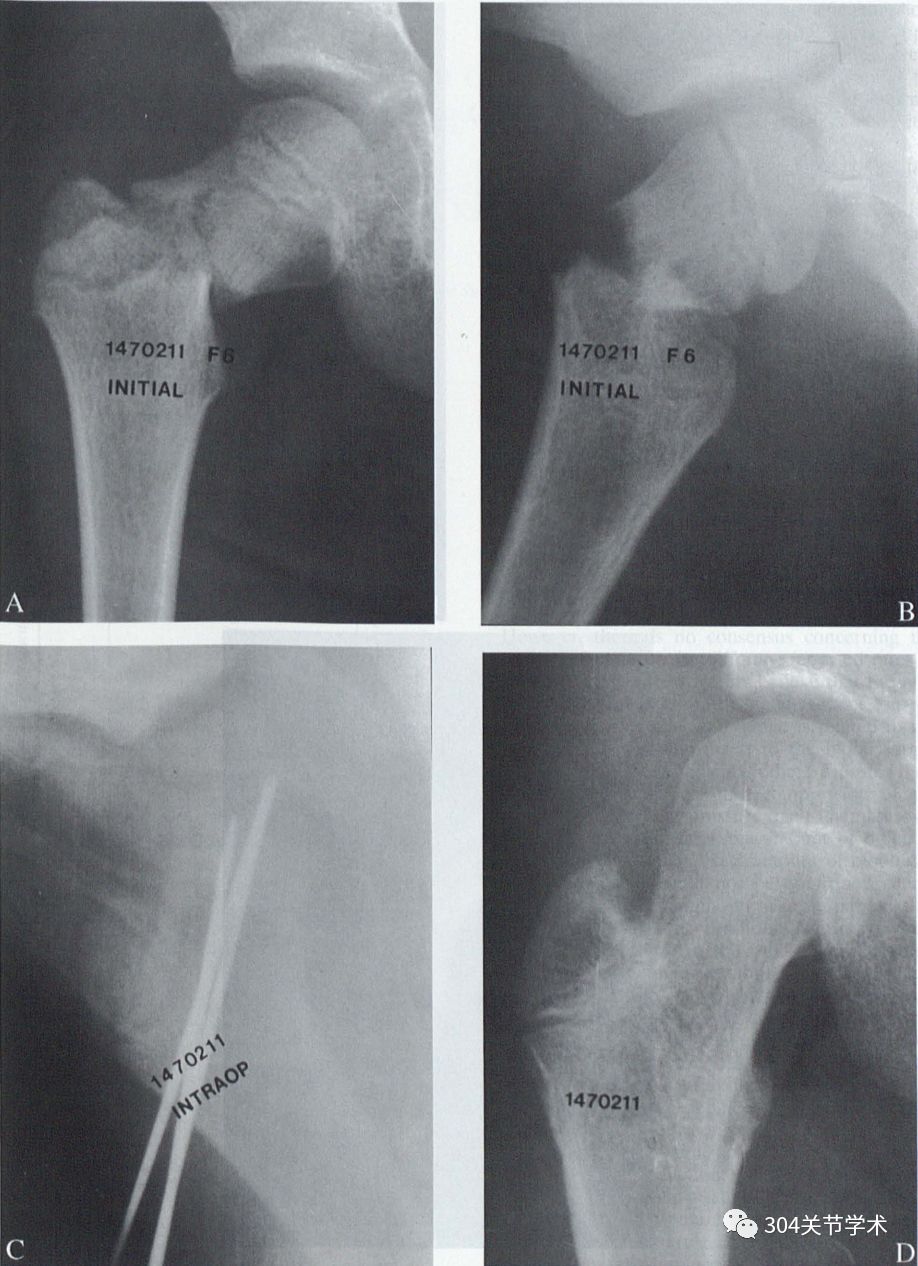

典型病例:6岁女,A、B显示III型移位型股骨颈骨折,移位程度占30%-40%;C 伤后48h内,行关节切开血肿清理,同时行切开复位克氏针固定术;D术后41月,骨折愈合无并发症发生。

Arthrotomy and open reduction of the displaced fracture of the femoral neck in children

The objective of the study was to examine the efficacy of limited arthrotomy coupled with open reduction and internal fixation to minimize potential complications of vascular disruption of the capital femoral physis and femoral epiphysis. It was a patient outcome study. Skeletally immature patients with femoral neck fractures were treated according to a protocol in which all patients underwent limited arthrotomy with decompression of the intercapsular hematoma, open reduction and internal fixation. Radiographic and magnetic resonance imaging studies were carried out on patients to assess whether avascular necrosis developed in the postoperative period. Patients were followed for a mean length of 2 years 8 months, with a range of 2 years to 5.5 years. Twelve patients had good results and one had fair results using Ratliff criteria. No patient developed avascular necrosis (ischemic necrosis), coxa vara, nonunion or premature epiphyseal closure. This study supports the hypothesis that limited decompression of the intracapsular hematoma in children with femoral neck fractures may be a factor in obviating the subsequent appearance of ischemic disruption of the epiphysis and physis.